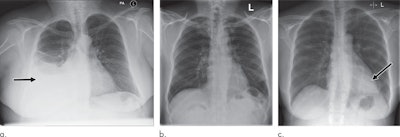

Examples of radiographs that were correctly and incorrectly prioritized by the AI system. A: Radiograph was reported as showing large right pleural effusion (arrow). This was correctly prioritized as urgent. B: Radiograph was reported as showing "lucency at the left apex suspicious for pneumothorax." This was prioritized by the AI system as normal. On review by three independent radiologists, the radiograph was unanimously considered to be normal. C: Radiograph was reported as showing consolidation projected behind the heart (arrow). The finding was missed by the AI system, and the study was incorrectly prioritized as normal. All images courtesy of Radiology.The researchers then assessed the system's performance for prioritizing radiographs in a computer simulation involving an independent set of 15,887 images. They simulated an automated radiograph prioritization system in which abnormal studies determined by the AI system to be critical or urgent could be automatically placed higher in the queue on the basis of their predicted urgency level and waiting time of other already queued radiographs.